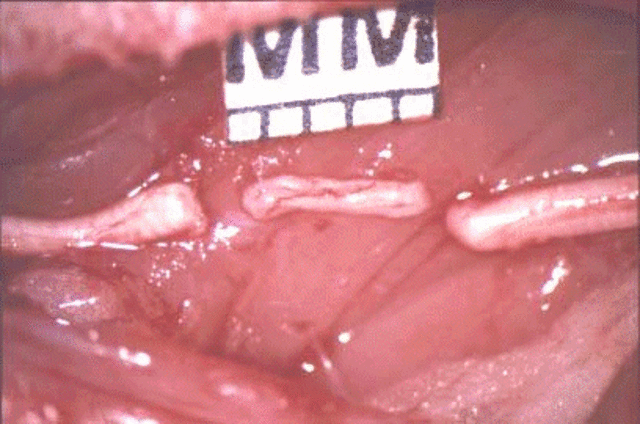

• Scope Surgery

Scope Surgery

The use of various scopes being used in surgery is becoming increasingly popular. The advantage to scope surgery is that minimal incisions need to be made.